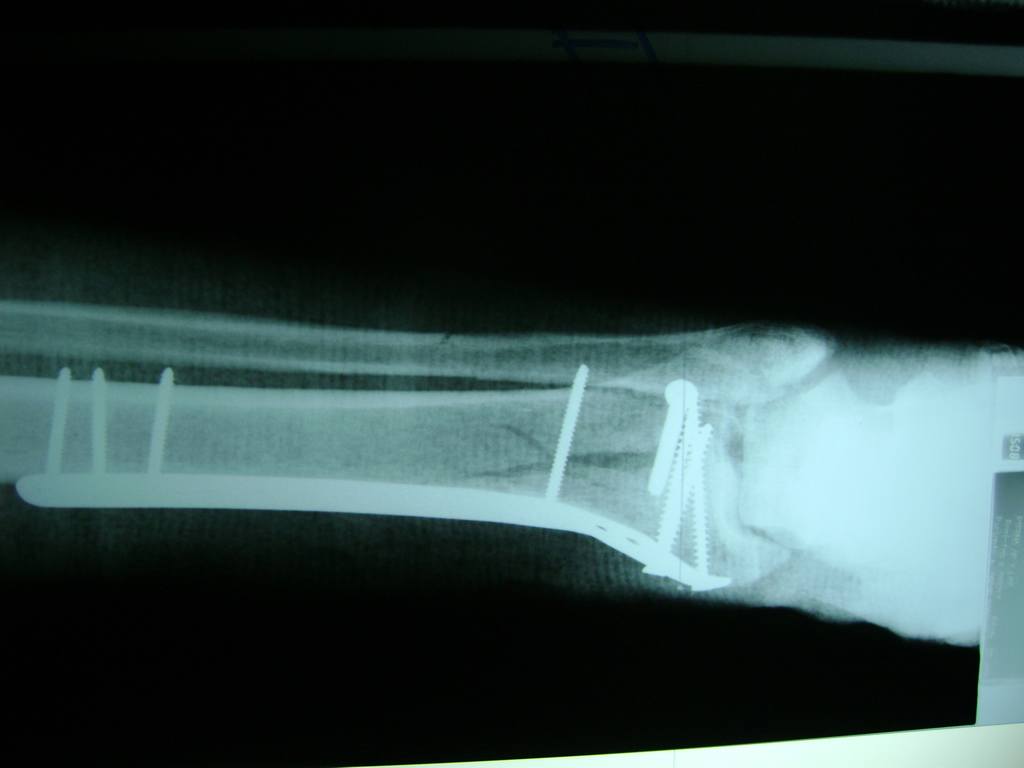

La mayor parte de las roturas implican a la parte proximal del hueso (parte del hueso próximo a la rodilla) o a la parte distal (parte del hueso cerca del tobillo).

Debido a la fina cobertura de piel que recubre la tibia y el peroné, las fracturas generalmente son abiertas, es decir, el hueso roto rasga la piel, atravesándola. Las fracturas de tibia y peroné generalmente se producen por un fuerte impacto o torsión.